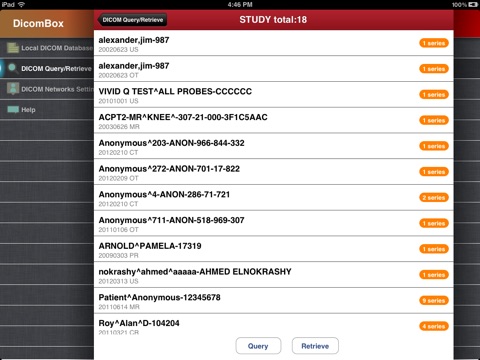

"DicomBox" is a DICOM software for iOS: DICOM is the digital standard for storing and transferring medical images. DicomBox allows downloading and manipulating series of images directly on your iOS device. DicomBox is capable of displaying images from all imaging modalities in their native standard DICOM format used by the medical/scientific industry. DicomBox is a fully DICOM-compliant listener that can receive images from any DICOM imaging device through WiFi/3G networks.